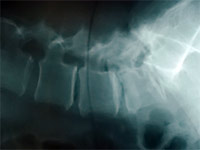

Bevor es zu der eigentlichen Operation kommt, wird in einem individuellen Aufklärungsgespräch der Eingriff an Hand der Röntgen und MRT-Befunde und die anschließende Nachbehandlung genau erläutert.